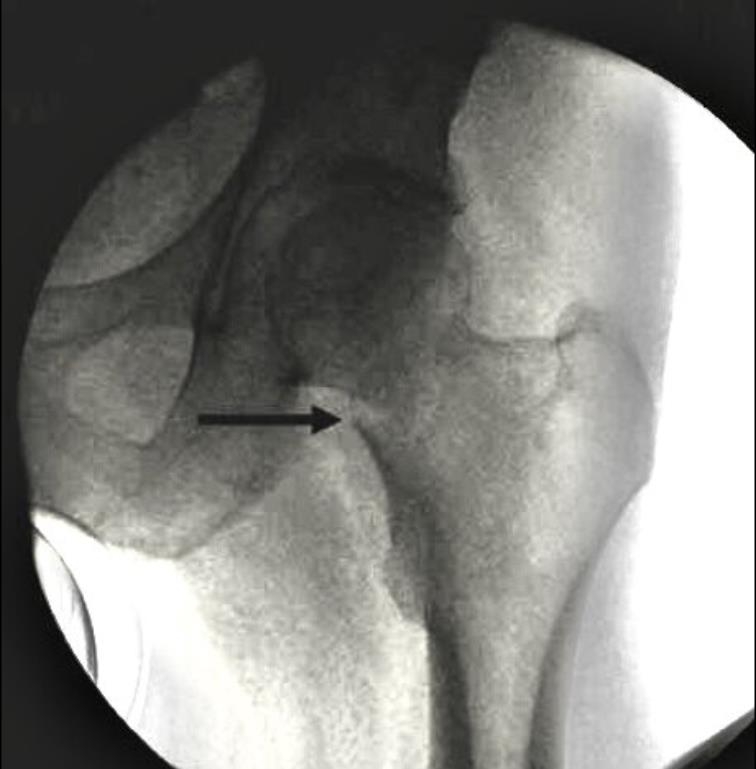

阳性支撑与阴性支撑

1、阳性支撑是指股骨颈骨折的远骨折端突向近侧骨折断端内下缘的内侧。

图3 阳性支撑更稳定